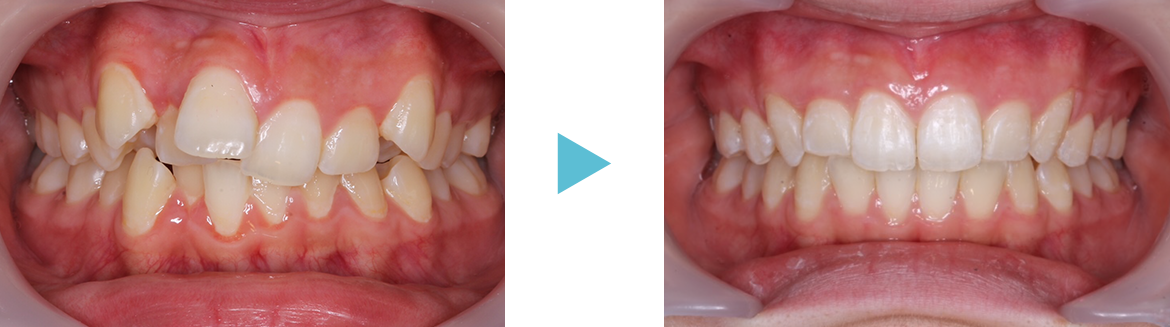

矯正用の拡大装置を使うと顎を広げる作用で歯並びも良くなりますが、鼻腔も広がるので口呼吸を改善し、様々な症状が改善する可能性があります。ぜひご相談ください。

固定式拡大装置は床タイプと違って自分で外せないので、確実に治療が進みます。 また床タイプでの拡大では傾斜移動になり根尖が動きませんが、固定式の場合は歯体移動ができ、鼻腔も広がる可能性があり口呼吸から鼻呼吸への改善可能性があります。